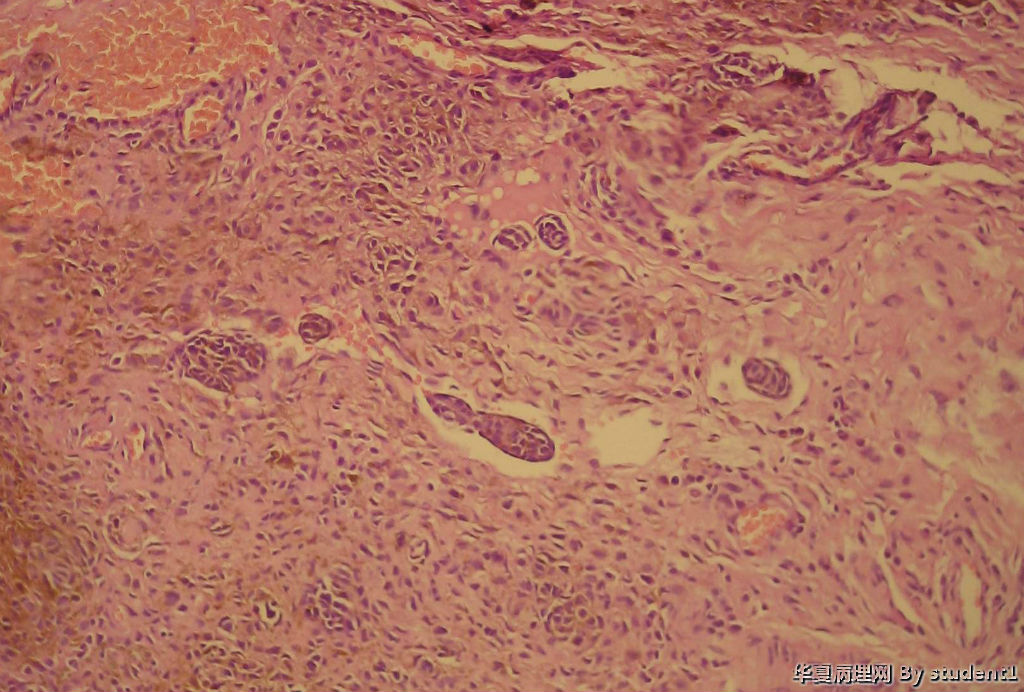

男,35岁,结膜痣切除

送检小组织,直径0.2cm

请教:是否侵犯血管淋巴管?有何意义?

结膜痣?图2

名称:图2

描述:10倍

皮内痣

考虑皮内痣,那些痣细胞巢周围未见内皮细胞,不考虑侵犯血管淋巴管。